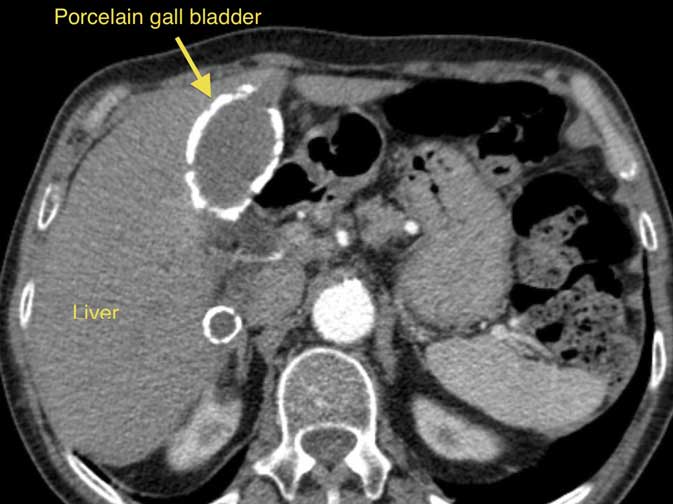

Calcium deposits in the wall of the gall bladder (a consequence of chronic inflammation), described as Porcelain gall bladder, increase the risk of gall bladder cancer. The picture on this page shows a CT scan, with a porcelain gall bladder clearly visible (you can click on the picture to enlarge it).